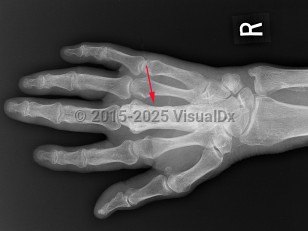

Paget disease of bone

The disease is often asymptomatic but can cause bone pain, fractures, bone deformity, and symptoms due to compression of surrounding structures (eg, hearing loss, lumbar radicular pain). Genetics and viruses are suspected to play a role in causing the disease.